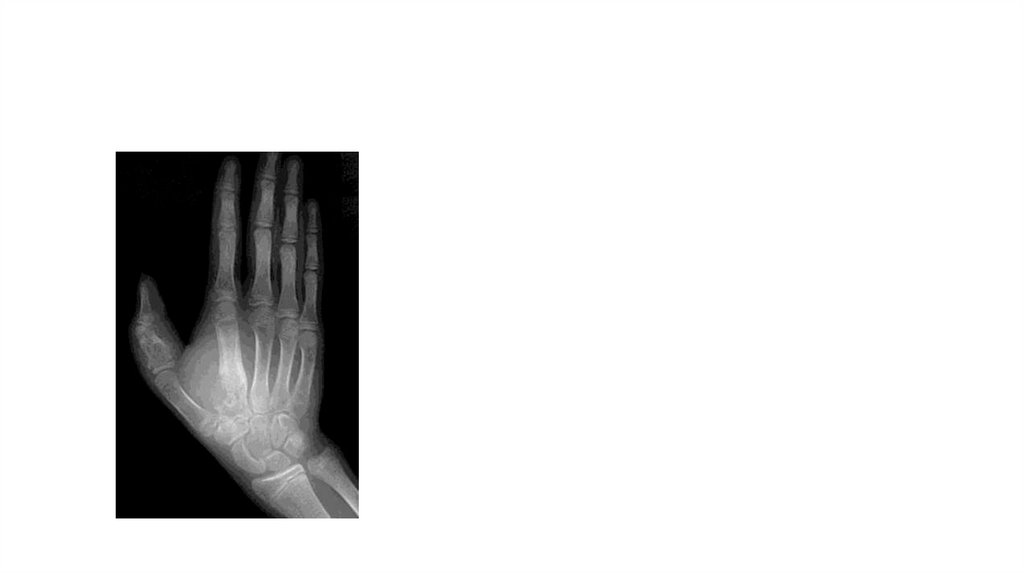

Воспалительные заболевания опорнодвигательного аппарата

«Воспалительные

заболевания опорнодвигательного аппарата»